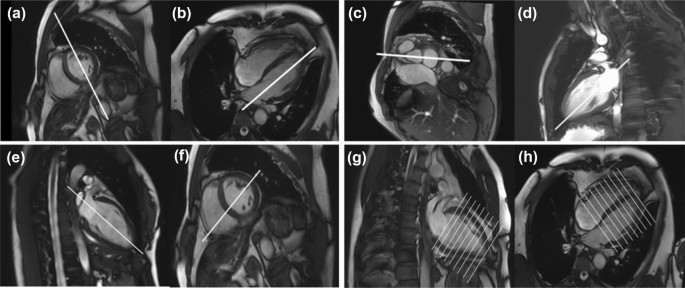

图一 心脏成像视图选择举例